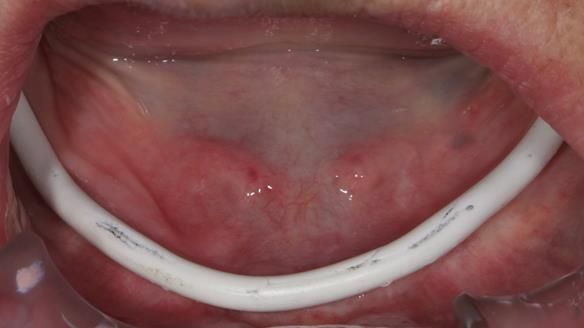

Welcome to Newsletter 83. This month I am sharing Sheila’s case — a very challenging but rewarding complete denture case. Sheila had flat ridges, a small mouth opening, a large tongue and had never been able to wear complete dentures of any kind. Everything was loose and sore. She felt embarrassed and looked older without dentures. She wanted a stable, comfortable result, and she wanted to avoid implants because she has taken bisphosphonates for more than five years.

Because her denture space anatomy was limited, I took two working impressions at the same visit. She had very little space in the lower jaw because of the spread of the tongue and the fact she had never worn a lower denture. This made it difficult to judge exactly where the borders needed to be and how much functional space we truly had.

I then made a second working impression using Dr John Besford’s neutral zone approach, known as the French Impression Technique. John learnt this from a dentist in Marseille called Hubert Aiche. I used this technique to record the functional position of the denture borders and tooth space in case the conventional method did not give a stable enough shape.

In Sheila’s case, the Dr Abe shaped impression gave a more stable and comfortable result. Sheila preferred the shape produced by the Abe method, so that is the one we used for the registration rims, the trial denture and the final dentures. But making both impressions was worthwhile. It meant we had every option covered and could choose what worked best for her mouth.